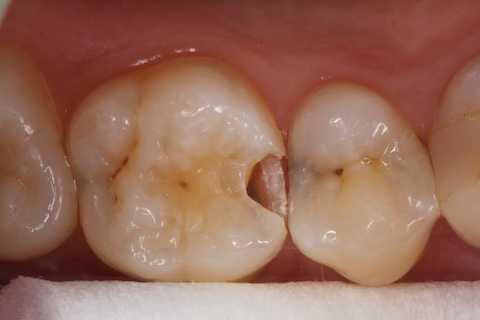

20代女性、右上6、咬合性外傷による隣接面カリエス

この歯は10年以上も削らずに様子を見ていたのだが、最近しみるようになったとかで、東京住まいだし、次帰れるのは年末か?コロナもあるし分からない、、ということなので、介入することにした。

クラックが気になるのだが、象牙質には広がっていないようだったので、このまま充填した。

隣の5番はエアブローでしみなかったので、そのままだ。

実像から

鏡像、クラック部分は拡大した。